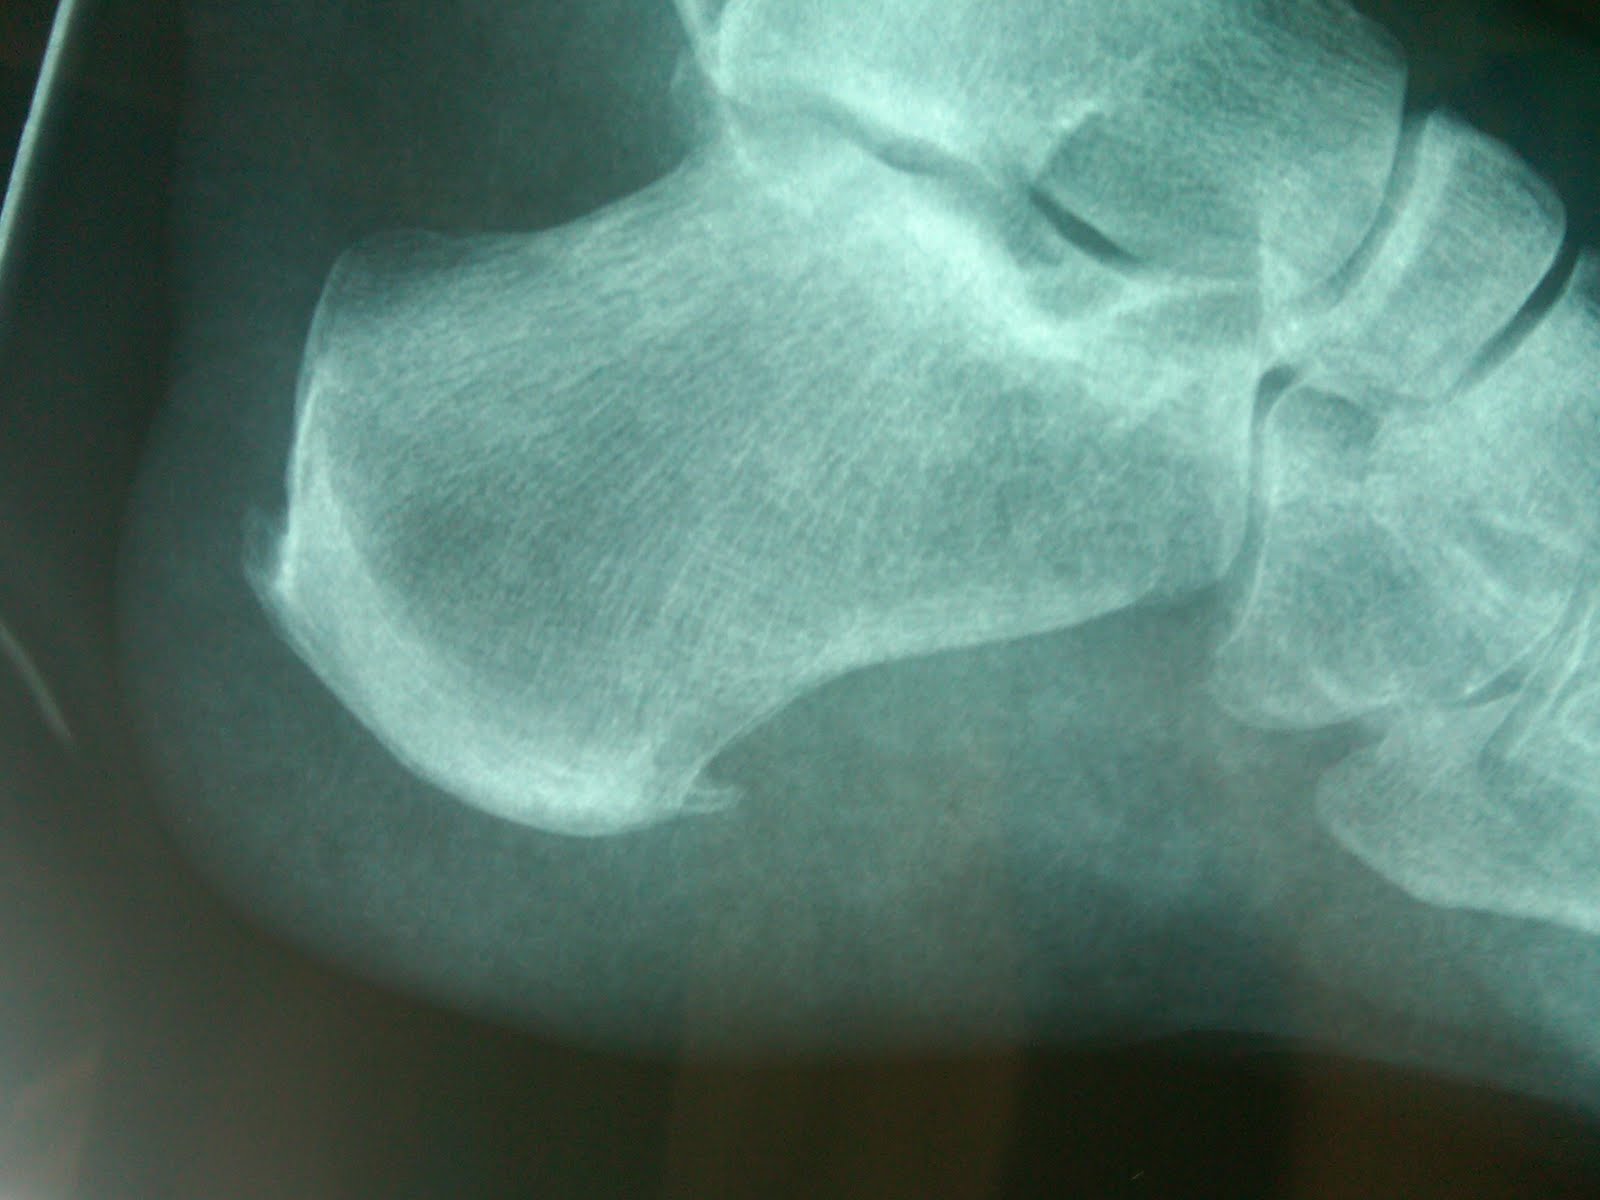

Ice Climbing Heel Spurs . Apply ice after activity to decrease pain in your heel. learn how heel spurs develop, what symptoms they cause, and what treatments can help you heal them. Use heat to increase blood flow before you perform your stretches. place your ice pack on your heel for 10 to 15 minutes at least twice a day. Find out about rest, ice, stretching, orthotics, footwear, medications, physical therapy, and medical interventions. Ice can help relieve pain and prevent. heat and ice are both beneficial for symptoms of heel spurs. heel spurs are calcium deposits on the heel bone that can cause pain and inflammation.